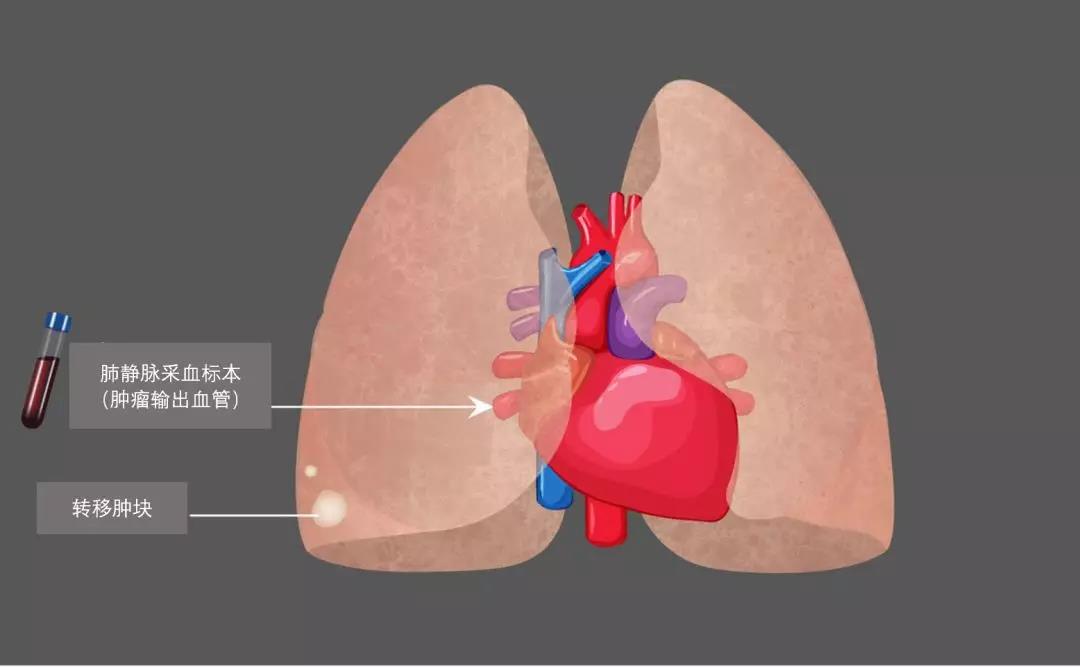

癌细胞从下腔静脉进入右心,并被输注到肺内,经过肺血管网络,一部分癌细胞留驻在肺内,形成结直肠癌肺转移癌。

从肺静脉回流到左心的血液,被射进主动脉,然后血液就快速地分布到全身,血液中的癌细胞,就被送往全身,并可能在体内某个部位或多个部位形成转移肿瘤,比如骨转移,脑转移,肾转移等。

他们在24个结直肠癌肺转移瘤切除手术中,采集了转移癌病侧肺静脉血液。他们采用CellSieve-microfilters技术、免疫组织化学和Giemsa染色,对22个标本进行了枚举CTC检测。另外10个血液标本采用CellSearch-System进行分析。他们从肺静脉中枚举到癌细胞数(总计41,在0-15个范围),远远超过同时在肢体血管采血检测到的癌细胞数(总计6个,在0-5个范围,P=0.009)。在所有检测到CTC病例中,研究人员发现,肺静脉血中的癌细胞与肺转移结直肠癌导致局部淋巴侵犯有显著相关性(P=0.006),也就是说结直肠癌肺转移,并发肺部淋巴结转移的病人,肺静脉内更容易筛查到癌细胞。

研究人员进一步发现,肺静脉里找到的癌细胞就是来自结直肠癌肺转移肿瘤,他们还证实从肿瘤流出血管中找到癌细胞,是一项代表病人预计后果很差的指标。